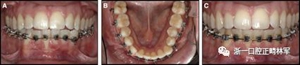

臨床檢查顯示固定保持器完好,弓絲沒有斷裂(圖13)。在下頜右側中切牙唇側和鄰近側切牙的舌側注意到有牙齦退縮。這些牙齒在退縮方向上存在顯著的扭矩差異。下頜的左側尖牙頰側錯位,而右側尖牙舌側傾斜。三維射線照片證實了下頜右側尖牙面?zhèn)妊啦酃菃适?,右側中切牙的喪失程度較輕。右側側切牙根也從舌側骨面上扭轉出來(圖14)。

圖13.粘合到尖牙和切牙上的柔性螺旋弓絲保持器,伴有牙齦退縮和附著喪失,中切牙之間嚴重的扭矩差異以及兩顆尖牙的橫向移動和扭矩。牙周問題和牙齒移動的嚴重程度均為牙周正畸聯(lián)合治療的指征:A,正面視圖; B,咬合面視圖。

粘合保持器被移除,并放置固定裝置(圖15),僅限于患者要求的下頜弓。在第一階段牙周過程中,將結締組織移植物置于下頜右側中切牙的面?zhèn)取?個月后進行第二階段牙周過程(圖16)。包括有意識的垂直骨質評分以啟動區(qū)域加速現(xiàn)象,以及顯著的面?zhèn)群蜕鄠戎补且约m正骨開窗。隨著時間的推移,全維度弓絲及其表達的牙齒間扭矩差異顯著改善(圖17)。明智的鄰間減少之后,間隙關閉擴大接觸面,消除不美觀的黑三角。在脫粘之前也校正了牙齒排列和牙弓形態(tài)(圖18)。之前和之后的三維圖像(圖19)突出顯示在下頜右側尖牙面?zhèn)缺砻嫔瞎堑脑黾右约扒把姥栏恢玫母纳啤S捎谙骂M切牙的伸長被認為是不嚴謹?shù)?,因此輕度前牙開合沒有被矯正。